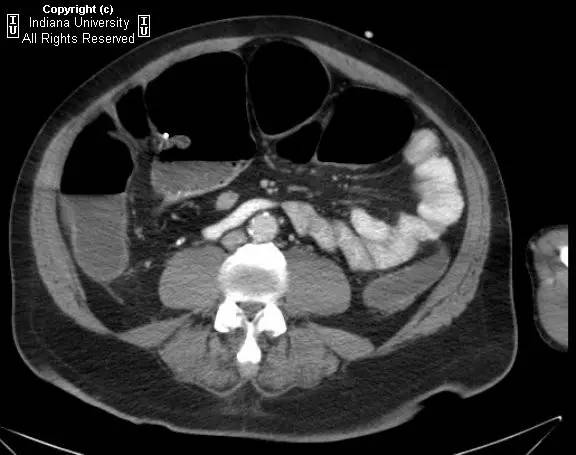

【影像学表现】右侧腹部可见曲线样不透亮区,1周后位置有变化(似进入盲肠)。横结肠显著扩张、充气。CT上扩张原因不明,无明确的梗阻证据。

【诊断】阑尾内对比剂充填